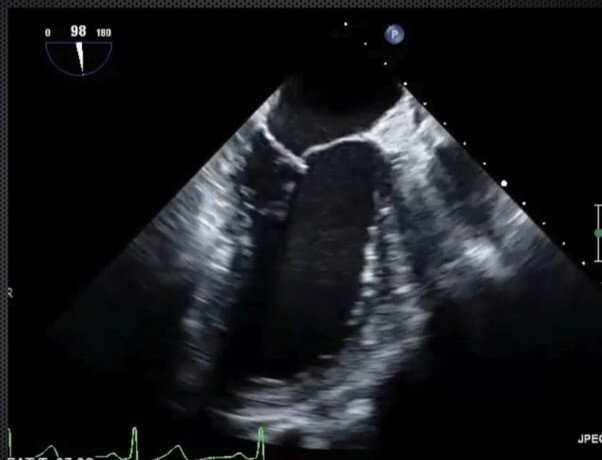

Mid-Esophageal Bicaval view

- RA, LA, IVC, SVC - Start with ME RV inflow/outflow and multiplane to 90-110 degrees, rotate probe clockwise. Good for looking for thrombus in the IVC/SVC, looking for appropriate pacing wire placement in RA.